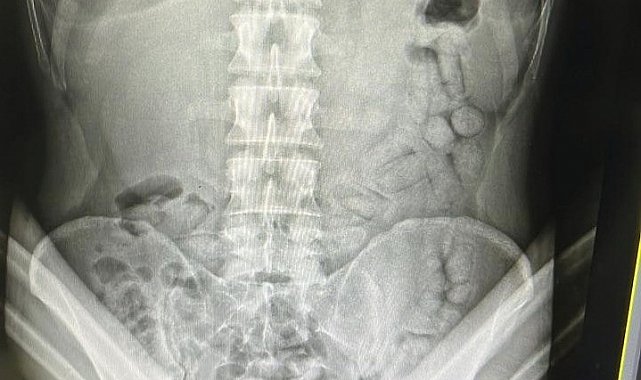

Adli makamların talimatı üzerine Gümüşhane Devlet Hastanesine götürülen şahsa yönelik iç beden muayenesinde bağırsaklarında 55 adet kapsül olduğu tespit edildi. Hastanede yapılan müdahalenin ardından şahsın bağırsaklarından çıkarılan kapsüllerin içerisinde toplamda 317,46 gram metamfetamin ele geçirildi.

Bağırsaklarında 55 adet uyuşturucu dolu kapsül çıkan İranlı şahıs tutuklandı